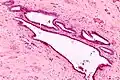

It is characterized by cysts with tubal-type epithelium (e.g. ciliated epithelium) surrounded by a fibrous stroma. It is not often associated with hemorrhage.

Intermed. mag.